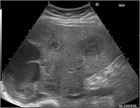

1. 転移性肝癌とは肝臓以外に発生した悪性腫瘍が肝臓に転移したものをいう。

1. 腹腔内臓器から門脈血流を受ける臓器であるため、消化器癌(大腸癌、胃癌、膵癌、胆道癌、食道癌など)からの転移の頻度が高い。